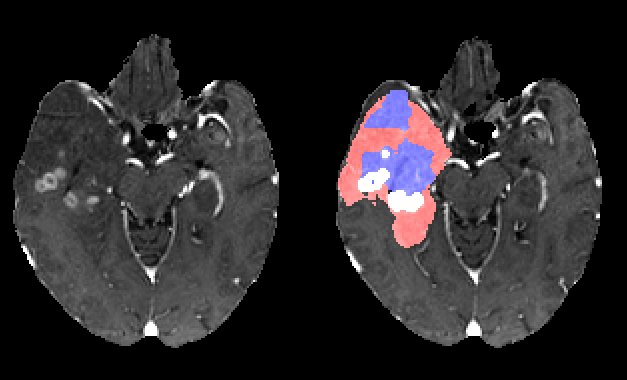

The segmentation ground truth provided with the BRATS 2017 dataset presents however some imperfections. The segmentation is relatively noisy and does not present a strong 3D coherence as illustrated in figure 5. We have thus decided to manually smooth each ground truth segmentation map independently such that:

Due to our training data preparation (class wise segmentation smoothing) and due to our data augmentation method (additive noise), our segmentation results tends to be smoother than the ground truth segmentation. This effect is illustrated in figure 6.

Different segmentation results are illustrated in figure 7. The proposed network tends to produce smooth and compact segmentation results which are often very close in terms of Euclidean distance to the ground truth segmentation. We have consciously chosen to privilege this effect by smoothing the ground truth segmentation and augmenting data with additive noise. Different approaches may be better suited for other kind of quality metrics.